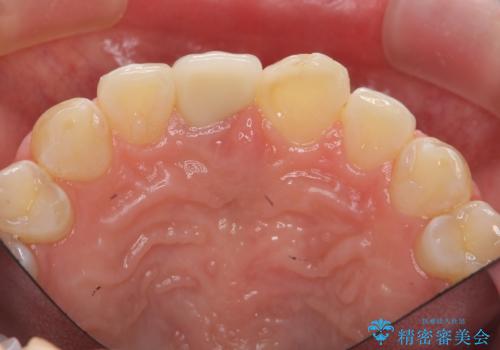

前歯をきれいにしたい ジルコニアクラウンによる審美治療

- 前歯の見た目の改善を求めて来院されました。

ジルコニアクラウンによる審美性の改善を計画します。

失活歯のため捻転を改善し、根管治療は特に希望されなかったのでそのままとしました。

今回失活歯であったため捻転を取り反対側の前歯に揃えて補綴を行うことができました。